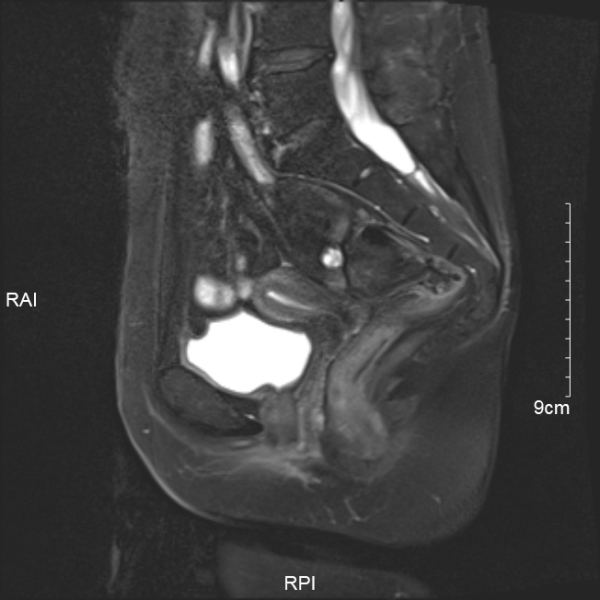

2024.12.6我院盆腔增强MRI提示子宫内膜局部不均匀稍隆起增厚,请结合临床及内镜(如下图所示)。